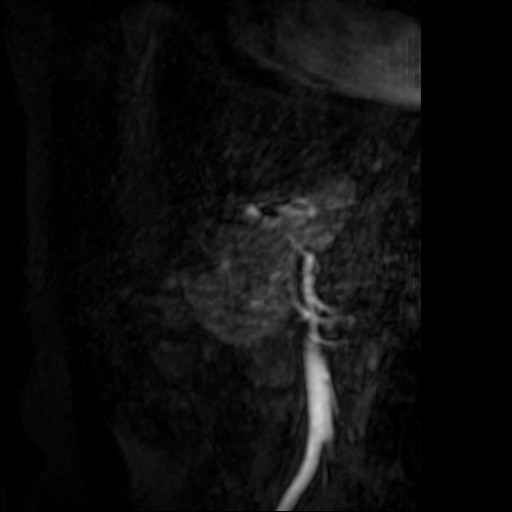

Angio abdominaal